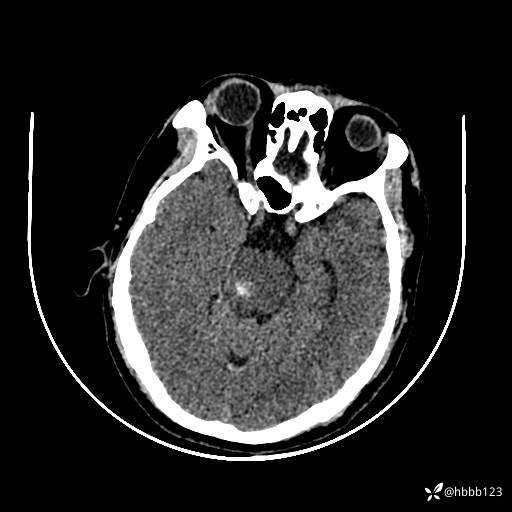

患者男,51岁。

简要病史:患者自述于1周前至某人民医院发现脑干肿瘤(具体不详),为求进一步诊断至我院就诊。

完善颅脑MRI平扫+增强,颅脑CT平扫:

颅脑CT平扫: